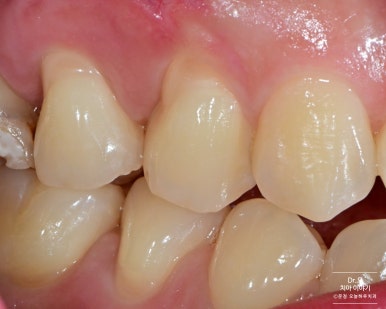

▶ 케이스 1: #14, 15 치경부 레진 치료

- 환자분은 시림 증상 없이 정기적으로 수복을 받고 계신 분이었습니다.

- 패인 부위 주변까지 넓게 레진으로 수복해 심미성과 유지력을 높였습니다.

치료 전 / 후 사진 비교

보시다시피, 단순히 패인 부분만 메우는 게 아니라

전체적인 윤곽과 색조까지 자연스럽게 회복한 것이 특징입니다.